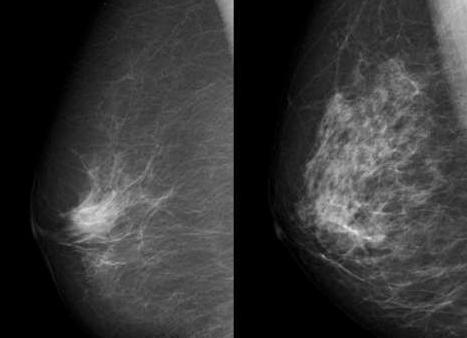

Инфильтративный протоковый рак молочной железы

Является наиболее распространенной (около 80%) формой в числе всех злокачественных новообразований груди. Чаще встречается среди женщин старших возрастов.

Он характеризуется множеством типов морфологической структуры и развивается из эпителиальных клеток молочных протоков, но затем способен распространяться на остальные ткани. Эта форма макроскопически представляет собой плотный овальный узел с неровными звездчатыми очертаниями, спаянный с окружающими тканями. Его наибольший диаметр может составлять от  0,5 до 10 см.  Внутри узла возникают некротические участки, в результате чего формируются кистозные образования, и отложение кальциевых солей (микрокальцинаты).

Длительное время опухоль ничем себя не проявляет и не определяется пальпаторно. Со временем в процессе роста она достигает ареолы или соска, что приводит к деформации или втяжению последнего, а также к появлению из него выделений, имеющих различный характер, как по консистенции, так и по цвету. Возможно формирование симптома «лимонной корки». Основные гистологические варианты опухоли: высокодифференцированная, низкодифференцированная, наиболее опасная в плане рецидивирования и метастазирования, и промежуточная.

• маммография (для старших женщин, на снимке можно выявить характерную россыпь кальцинатов);